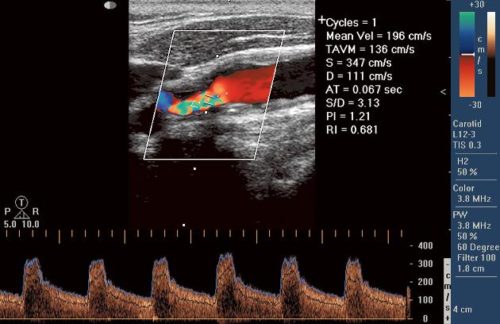

Расшифровка результатов

Полученные результаты обследования сравнивают со стандартными показателями нормы для каждого сосуда в отдельности. Основные показатели:

- индекс резистентного сопротивления;

- характер движения крови;

- качество крови;

- пульсационный индекс;

- диастолическая и систолическая скорость;

- синхронность движения крови в одноименных сосудах;

- диаметр сосуда;

- толщина сосудистой стенки.

На основании этих показателей выставляют диагноз. При обследовании беременных показатели сравниваются в нормой, соответствующей каждой неделе. Если в ходе обследования обнаружены тромбы, то определяют степень закупорки сосуда, структуру тромба, его тип (подвижный, пристеночный).